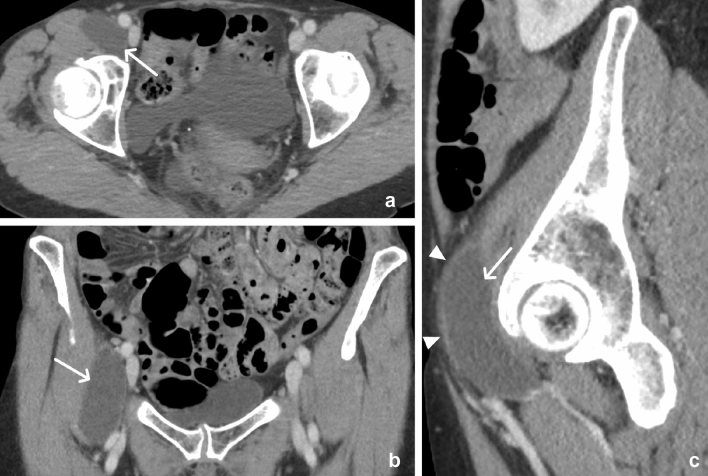

Fig. 6.

65-year-old female with iliopsoas bursitis. Axial (a), coronal (b), and sagittal (c) CT images demonstrate a well-defined cystic structure (arrows) with a thin mildly enhancing wall (arrowheads) that lies anterior to the hip joint and posteromedial to the iliopsoas muscle

Iliopsoas bursitis

Although not truly a muscular lesion, it is important to distinguish iliopsoas bursitis from other rim-enhancing lesions described here, such as myonecrosis and abscess. The iliopsoas bursa is a large synovial bursa located between the musculotendinous portion of the iliopsoas muscle and the anterior capsule of the hip [11]. Iliopsoas bursitis refers to inflammation of the bursa and is characterized by distension of the bursa [11]. Imaging findings include a well-defined, thin-walled, cystic mass with a communication to the hip joint which may have peripheral contrast enhancement [12] (Fig. 6).